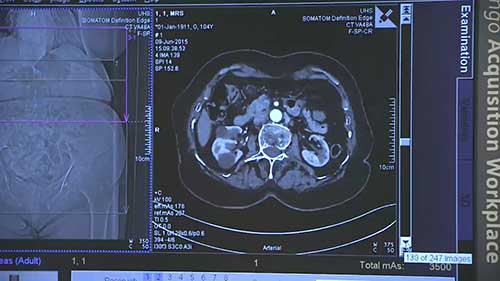

西门子多层螺旋CT

时长:4 分钟

类别:智能医疗装备技术

简介:德国西门子64排128层螺旋CT(SOMATOMPerspective)具有扫描速度快、图像清晰度高、低辐射和信息量大、临床应用领域广泛等优势。

双源CT的特点

双源CT是通过两套X射线球管系统和两套探测器系统同时采集人体图像的CT装置。来快速了解一下双源CT机的特点。